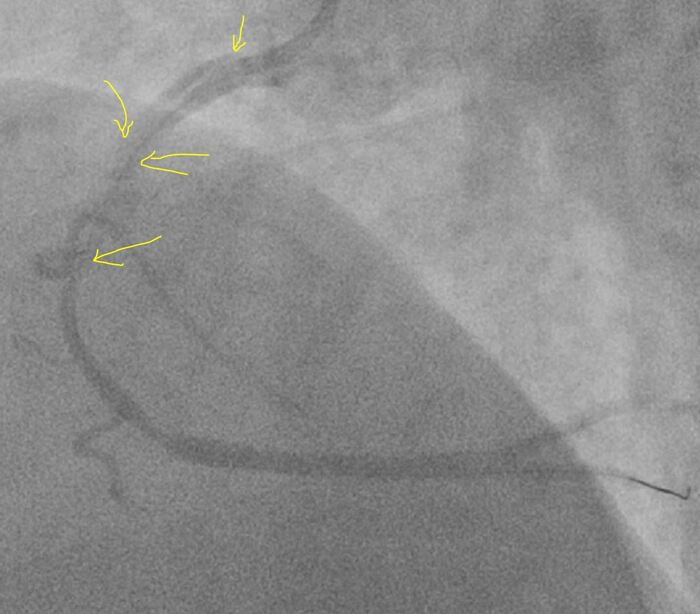

Не успел⁠⁠

8 утра, мужчина 66 лет, боли в груди с 3 ночи, скорая, в машине 7 раз фибрилляция желудочков, ЭДС, перевод на ИВЛ, с приемника на стол на коронарографию, при перекладывании опять остановка, наружный массаж, адреналин, ЭДС, пункция по ориентирам, введен катетер и такая картина - закрыты все три артерии, сердце стоит, на ЭКГ электрическая активность сохранялась еще минут 15 (электромеханическая диссоциация). На вскрытии циркулярный инфаркт, шоковые органы.

Upd: пояснения к видео (многим непонятно что произошло)

Желтые стрелки места закупорки коронарных артерий, цветные контуры - то как примерно должны выглядеть коронарные артерии в этой проекции (прямая) с пояснениями где и что. Движение на видео грудной клетки - работа аппарата ИВЛ.